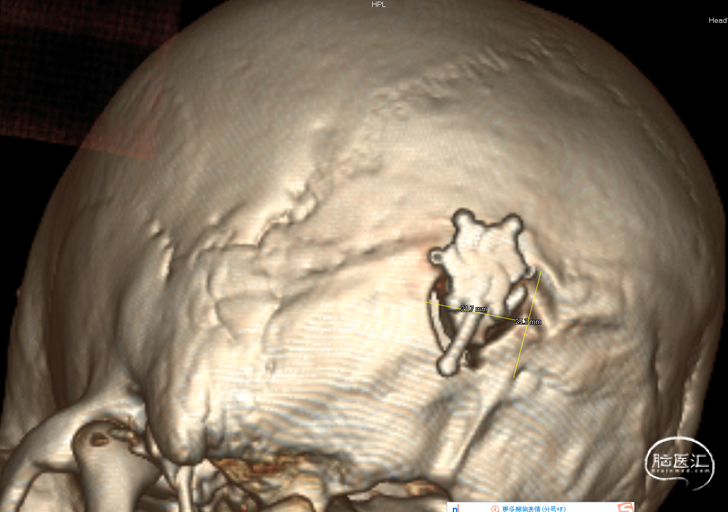

病人出血两次,第一次出血采取保守治疗。第二次出突发疼痛来住院,做了导航下的微创手术,海绵状血管瘤边界清晰,可见明显黄染。手术过程顺利,止血彻底。术后两次病理检查发现海绵状血管瘤,第二次手术中发现明显团块,术后恢复良好。